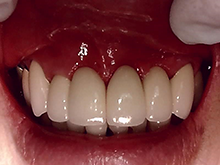

セ ラ ミ ッ ク ク ラ ウ ン

内面には金属を使用し、外面にセラミックを築成するタイプで、従来多くがこの方法で治療されていました。